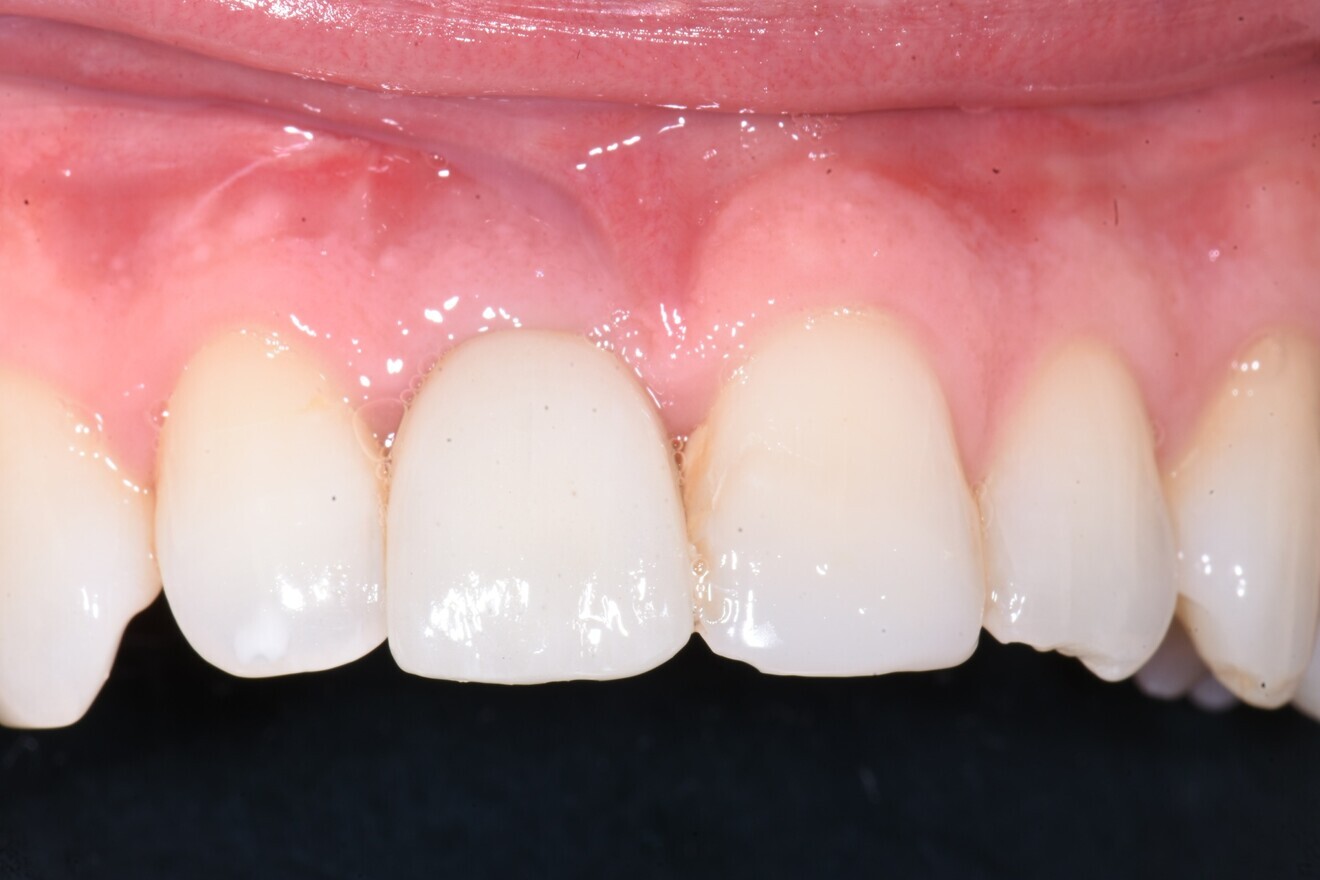

At this stage, impressions were taken using an intra-oral scanner, and the definitive screw-retained crown was fabricated utilising an Atlantis CAD/CAM abutment (Dentsply Sirona) and a bonded zirconia crown (Fig. 12). RFA was performed again at nine months and one year after placement, resulting in further increases to 85/84 ISQ and 86/86 ISQ, respectively. This plateauing of the ISQ values indicated that the graft had matured and complete secondary stability had been achieved. Thus, at the 12-month follow-up, not only was the patient satisfied with the aesthetics of the fixed restoration, including the enhanced soft-tissue profile, and the favourable radiographic outcome (Fig. 13), but we also gained insightful and detailed information on implant stability from the longitudinal ISQ values, giving us confidence in the long-term prognosis of this implant-supported restoration.

Fig. 12: Definitive screw-retained zirconia crown on an Atlantis CustomBase milled titanium abutment.